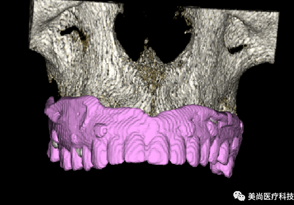

A.将CBCT数据导入软件中

C.添加模型数据

D.图像拟合

5.种植模拟设计